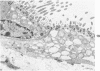

The morphogenesis of pulmonary lesions and associated edema induced by the pulmonary toxicant 3-methylindole (3-MI) was studied by combined light and transmission electron microscopy. Weanling male CD-1 mice received 3-MI dissolved in corn oil by intraperitoneal injection and were studied at intervals from 2 to 360 hours after treatment. Interstitial edema was observed as early as 2 hours and was associated with focal cytoplasmic swelling and membrane alterations in both capillary endothelial cells and Type I alveolar epithelial cells and with sequestration of neutrophils. Cell swelling, cytoplasmic fragmentation, and necrosis of Type I epithelial cells was most severe at 24-48 hours after treatment. Multifocal hypertrophy and hyperplasia of Type II alveolar epithelial cells was observed at 24-96 hours after treatment. Platelet aggregation and aggregates of fibrin were frequently observed in capillaries and small arteries and veins as early as 4 hours and as late as 48 hours after treatment. In airways, the nonciliated bronchiolar epithelial (Clara) cell was the predominant cell affected. Initial lesions in nonciliated cells consisted of loss of microvilli and secretory granules followed by marked swelling of the endoplasmic reticulum and mitochondria. Necrosis of cells lining airways was most pronounced at 24-48 hours after treatment. By 144 hours after administration, pulmonary repair was complete. It is concluded that the mouse is a useful model of 3-MI-induced pulmonary injury and that damage to both Type I alveolar epithelial cells and capillary endothelial cells is important in the pathogenesis of 3-MI-induced pulmonary edema.